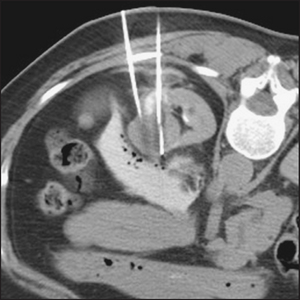

Some common renal scan findings are presented in Figures 19.4–19.8.

Figure 19.7 CT scan of renal tumour showing needles used for ablation treatment (From Allan PL, Baxter GM. Clinical ultrasound, 3rd edn. Churchill Livingstone, 2011.)